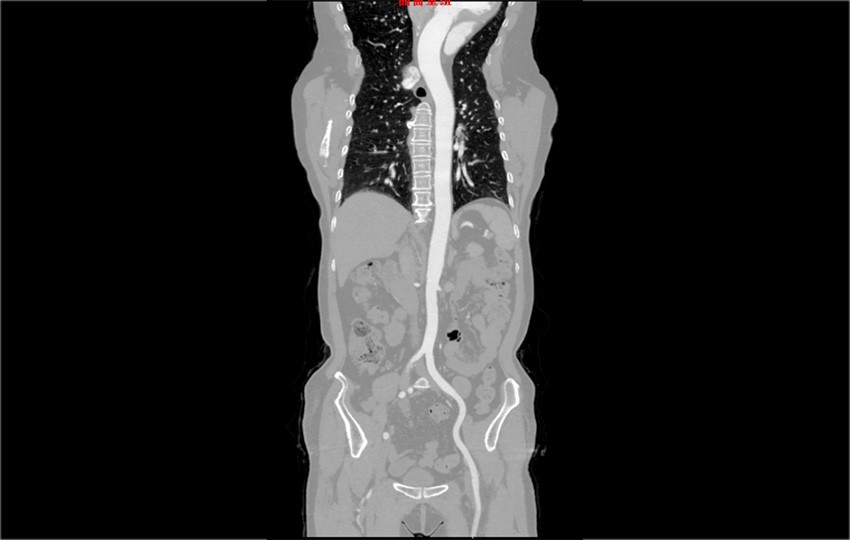

Пример 1-1<br>КТ Ангиография Грудной Клетки и Брюшной Полости

КТ Ангиография Грудной Клетки и Брюшной Полости